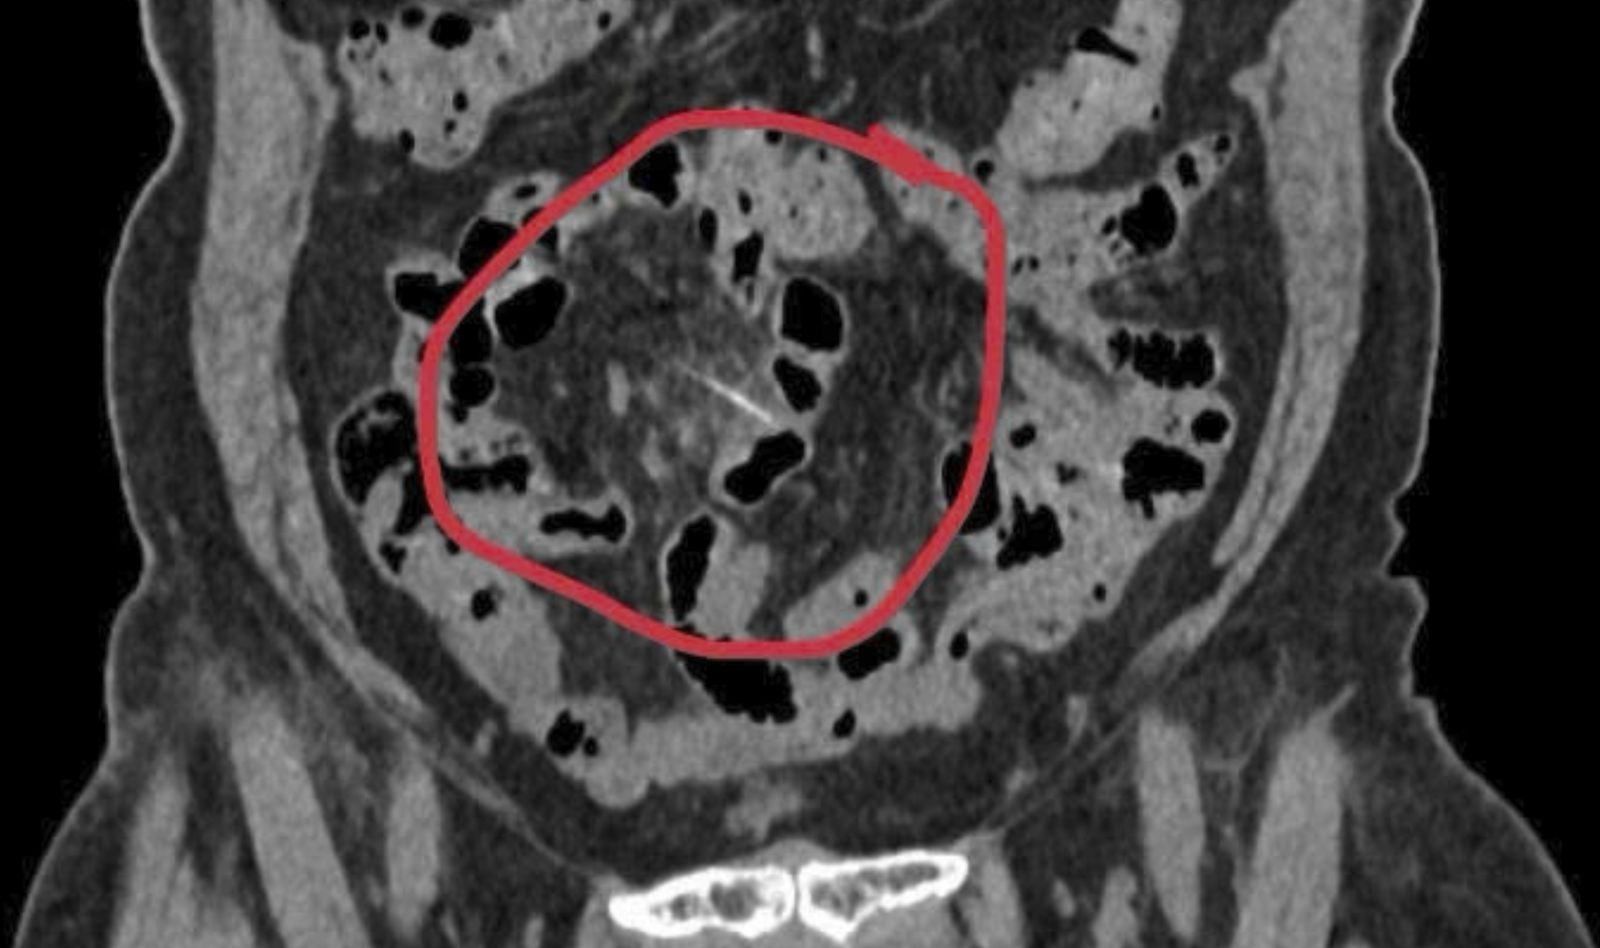

Chụp cắt lớp vi tính phát hiện dị vật dài khoảng 3cm nằm trong đoạn cuối ruột non – nghi là xương cá trong ruột cô Xuyến.

Hình ảnh trong phẫu thuật gắp mảnh xương cá đối nằm trong đoạn cuối ruột non của người bệnh Xuyến.